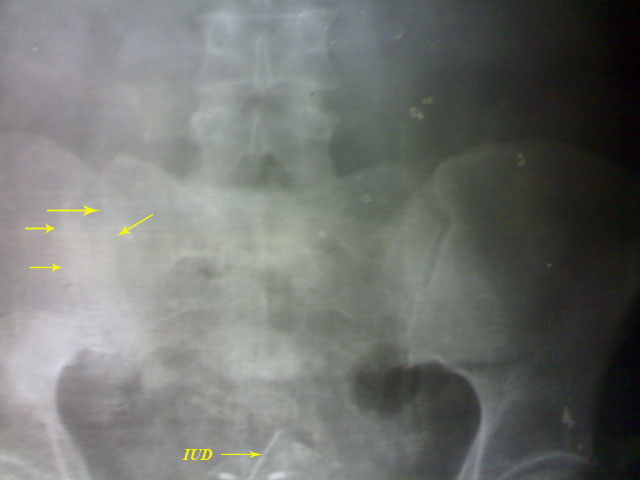

A case of unilateral sacroiliitis. No

other clinical data of significance.

For MRI sacroiliac joints.